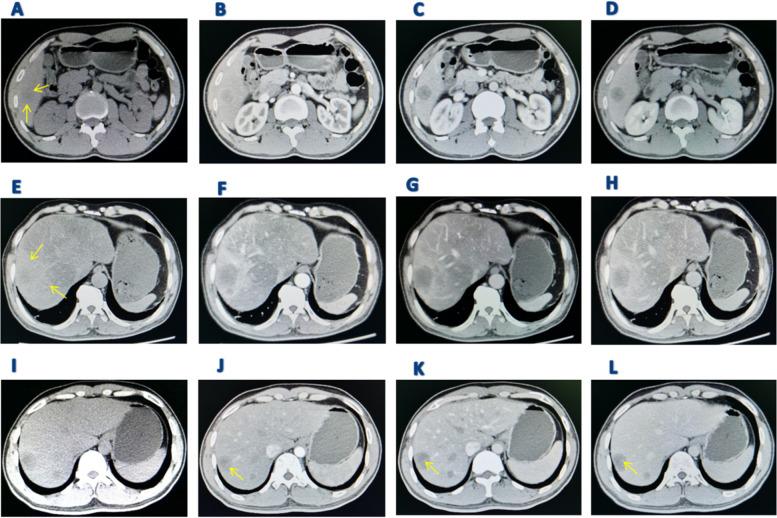

Among the 7 patients with PHA, 4 presented with a single solid intrahepatic mass (2 of which were large), 1 with a single exophytic macroblock type, 1 with a mixed type featuring multiple masses and nodules, and 1 with a multiple nodule type. Conventional ultrasound of PHA showed uneven echoes within the tumor, potentially accompanied by septal zone echoes, and a blood flow grade of 0-I. CEUS displayed early-stage circular high enhancement, a central non-enhancement area, and a "vascular sign" around the tumor. CT scans revealed low-density shadows in the plain scan stage, high peripheral ring enhancement, and punctate nodular enhancement in the arterial phase, with varying intensities and the presence of a "vascular sign." During the portal vein stage, the interior of the tumor was consistently unfilled and exhibited structural disorder. PET-CT showed low-density lesions in the liver and low fluorodeoxyglucose metabolism.

在 7 例 PHA 患者中,4 例表现为单个实性肝内肿块(其中 2 个为大肿块),1 例为单个外生巨块型,1 例为混合多个肿块和结节型,1 例为多发结节型。PHA 的常规超声表现为肿瘤内回声不均匀,可能伴有间隔区回声,血流分级为 0-1 级。CEUS 显示早期呈圆形高增强,中央无增强区,肿瘤周围呈“血管征”。CT 扫描显示平扫阶段为低密度阴影,高外周环增强,动脉期呈点状结节增强,增强程度不同,并存在“血管征”。门静脉期时,肿瘤内部始终未填充,结构紊乱。PET-CT 显示肝脏低密度病变和氟脱氧葡萄糖代谢低。